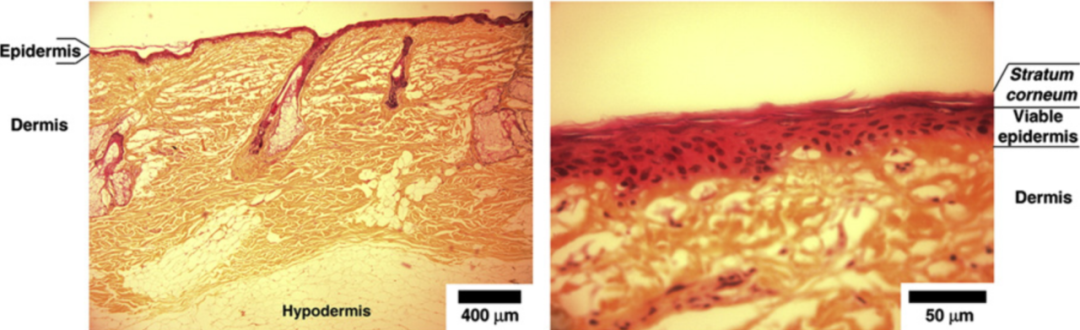

近些年較多的做法是直接使用組織切片機(jī)對(duì)實(shí)驗(yàn)皮膚進(jìn)行橫切,再分層測(cè)定濃度。然而,這種操作僅通過(guò)設(shè)定切片的厚度來(lái)實(shí)現(xiàn),但實(shí)際上皮膚各層組織的厚度可能存在個(gè)體差異,且各層之間的結(jié)合是交錯(cuò)的,并不是規(guī)整的平面,因此實(shí)際獲得的皮膚切片可能并不完全是所期待獲得的表皮層、真皮層等皮膚的生理結(jié)構(gòu)分層,據(jù)此方法獲得的數(shù)據(jù)可能存在一定局限。

【圖3】光學(xué)顯微鏡下皮膚組織學(xué)特征,表皮層與真皮層之間的界面并不平整